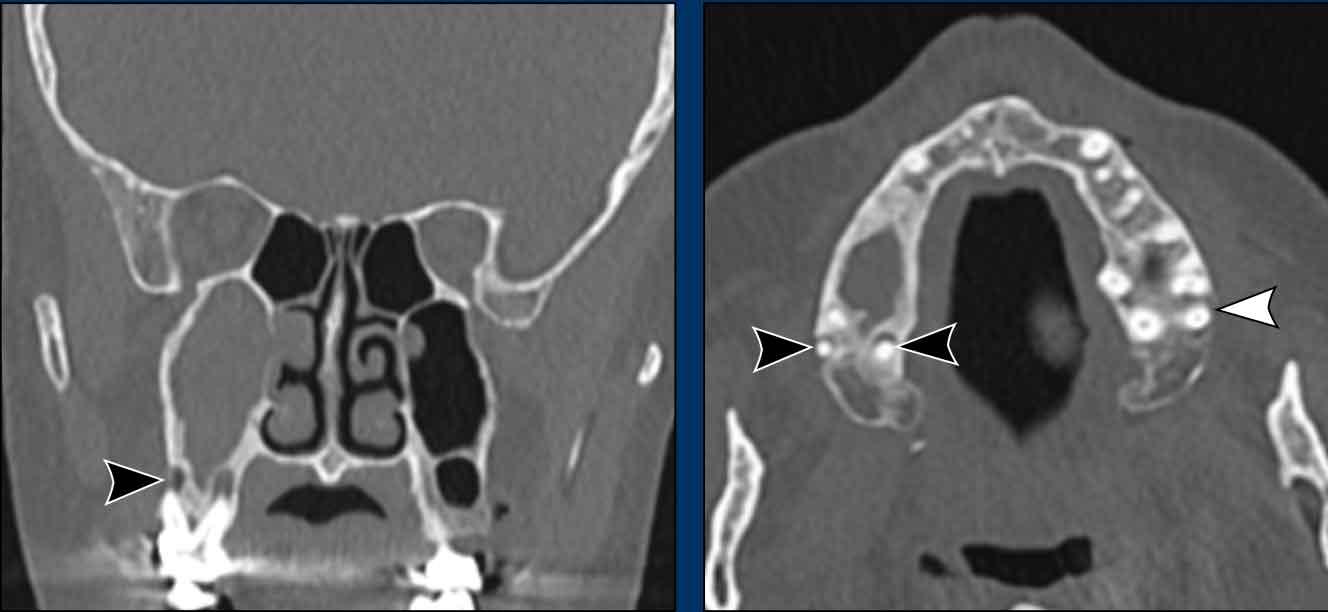

Bệnh nhân này có nang nhầy ở xoang hàm trái với giãn rộng nhẹ (mũi tên trắng).

Bên phải có một khối không có giãn rộng (đầu mũi tên vàng) và vẫn còn một ít khí trong xoang hàm.

Đây là nang ứ dịch.

Bệnh nhân này cũng có nang nhầy ở xoang hàm trái.

Bên phải có tình trạng lấp đầy hoàn toàn xoang hàm, nhưng không có giãn rộng.

Do đó, trường hợp này không đáp ứng tiêu chuẩn để chẩn đoán nang nhầy.

Các hình ảnh này của bệnh nhân nam 75 tuổi có triệu chứng nghẹt mũi và chảy máu mũi.

Hai dấu hiệu cảnh báo là:

- Phá hủy thành trong xoang hàm (mũi tên đen) và vách mũi (mũi tên trắng).

- Bệnh lý hoàn toàn một bên.

Ở bệnh nhân viêm mũi xoang, có thể có giãn rộng và đôi khi thậm chí phá hủy xương, nhưng bệnh lý (hầu như) luôn luôn xảy ra hai bên.